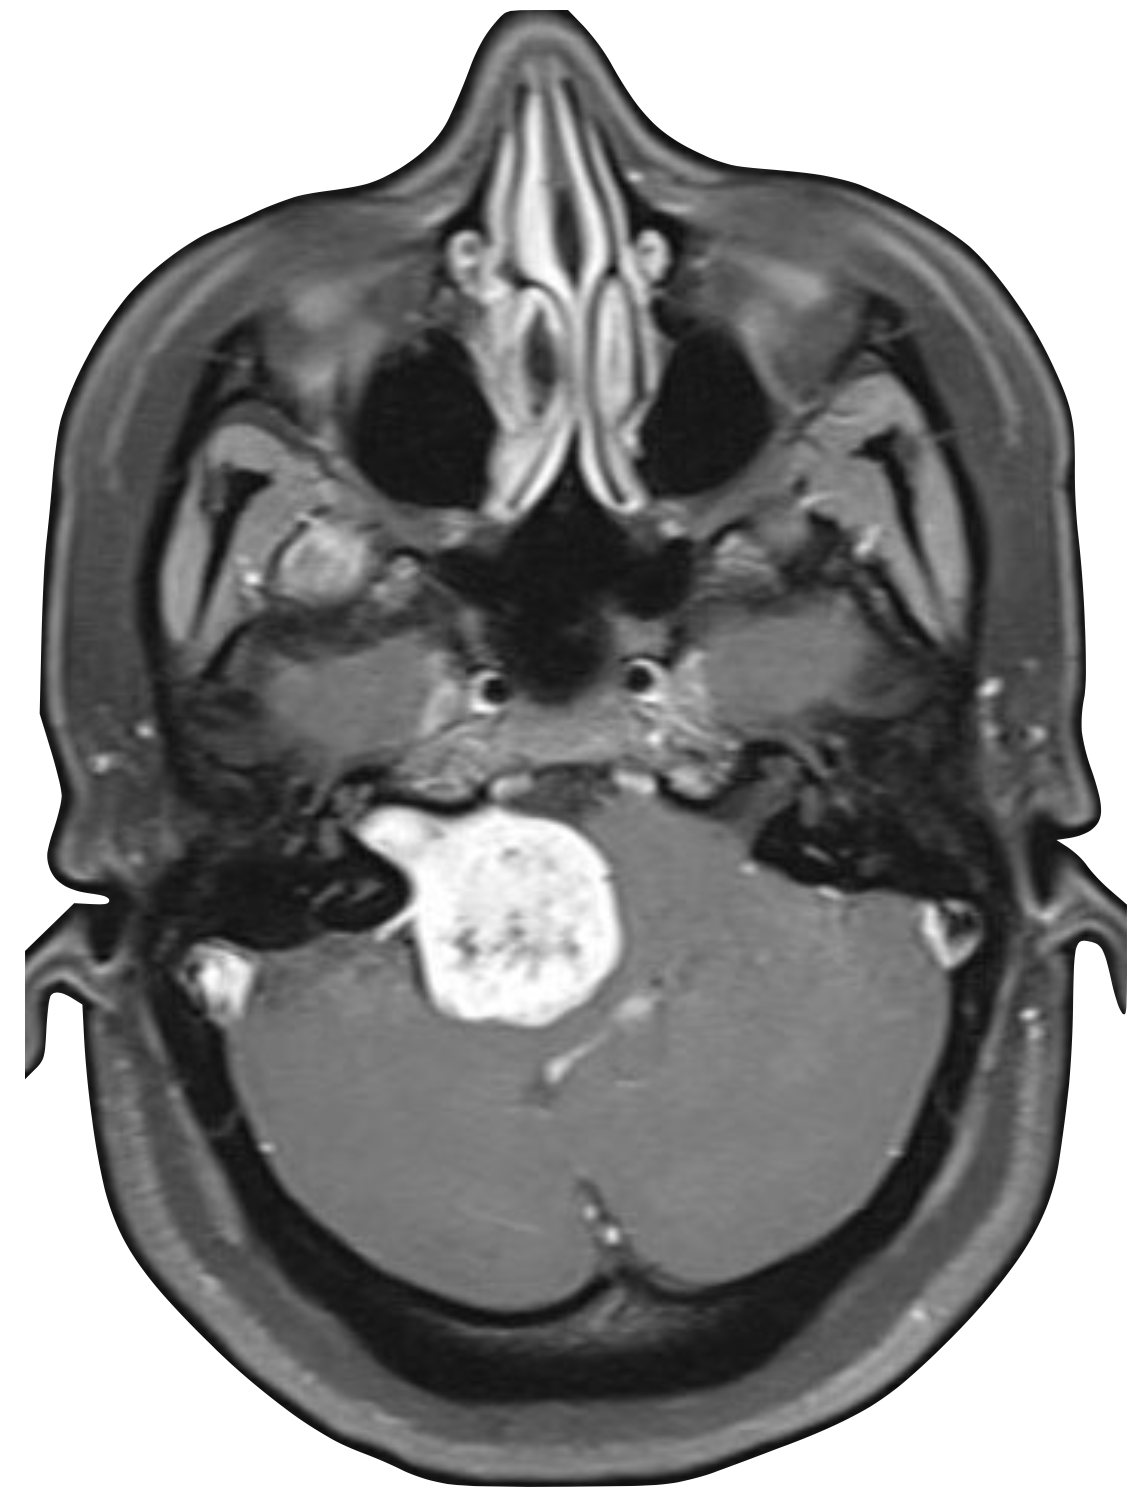

At Spokane ENT, we provide comprehensive evaluation and management of acoustic neuromas, also known as vestibular schwannomas. These benign tumors develop on the vestibular nerve that connects the inner ear to the brain, and our experienced team offers thorough diagnostic evaluation using advanced imaging techniques including MRI to accurately identify and characterize these tumors. We work closely with patients to understand their symptoms, which may include hearing loss, tinnitus, balance problems, and facial nerve concerns.

Our approach to acoustic neuroma treatment is highly individualized, considering factors such as tumor size, growth rate, hearing status, patient age, and overall health. We offer three main treatment options: observation with serial imaging for small, slow-growing tumors; stereotactic radiosurgery for medium-sized tumors or when surgery is not preferred; and microsurgical resection for larger tumors or when complete removal is indicated. Our team collaborates closely with neurosurgeons and radiation oncologists to ensure the best possible outcomes.

Treatment options include observation with serial MRI for small tumors, stereotactic radiosurgery for medium-sized tumors, and microsurgical resection for larger tumors. Your ENT will recommend based on tumor size, growth, hearing status, and your preferences.